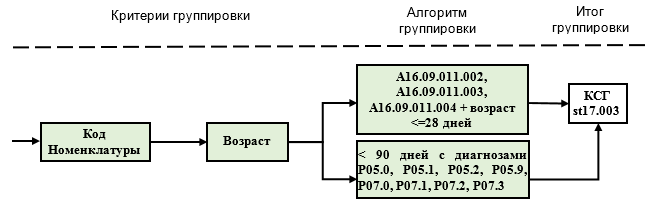

1-й аспект применения: диапазоны 1-3 используются для классификации случаев в КСГ st10.001 "Детская хирургия (уровень 1)", КСГ st10.002 "Детская хирургия (уровень 2)" и st17.003 "Лечение новорожденных с тяжелой патологией с применением аппаратных методов поддержки или замещения витальных функций":

- при возрасте ребенка до 28 дней (код 1) случаи классифицируются в КСГ st10.002 или st17.003 по соответствующему коду номенклатуры, независимо от кода диагноза.

- если ребенок родился маловесным, то по тем же кодам номенклатуры случай классифицируется в КСГ st10.002 или st17.003 при возрасте до 90 дней (код 2). При этом, признаком маловесности служит соответствующий код МКБ 10 (P05-P07), который используется как дополнительный диагноз (Код по МКБ 10 (2). В столбце "основной диагноз" может быть указан любой диагноз, который является основным поводом для госпитализации и проведения соответствующего хирургического вмешательства.